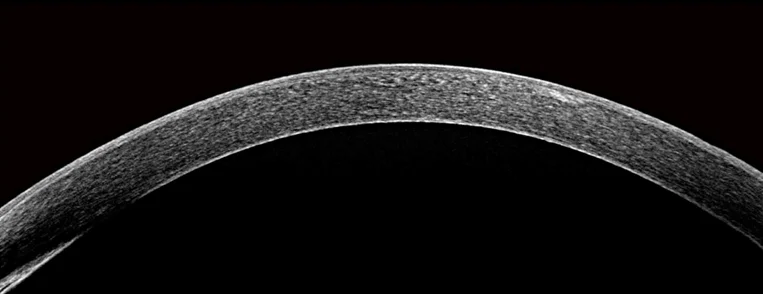

Anterior Segment Diagnosisd

9mm High-Definition Linear Scanning of Cornea of Anterior Segment Single-line

HD scan, multiple images combined to produce better image, clear cornea structure.Auto measurement and manual measurement for each cornea layer thickness.

Anterior Segment 16mm Angle-to-Angle Scan

Clearly showing the cornea and iris.

Accurate scanning of chamber angle, with high-definition display of the structure.